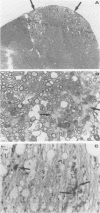

Theiler's virus, a murine picornavirus, persists in the central nervous systems of susceptible mice and induces a chronic demyelinating disease. Susceptibility or resistance to this disease is controlled in part by the H2-D locus of the major histocompatibility complex (MHC). For this reason, it has been proposed that CD8+ class I-restricted cytotoxic T cells play a main role in the pathogenesis of this viral infection. We recently reported the existence of anti-virus CD8+ cytotoxic T cells in the course of Theiler's virus infection. In the present study, we examined the role of these effector cells in mice in which the beta 2-microglobulin gene had been disrupted. These mice fail to express class I MHC molecules and therefore lack CD8+ T cells. The mice are derived from a C57BL/6 x 129/Ola cross and are H-2b, a haplotype associated with resistance to Theiler's virus infection. beta 2-Microglobulin-deficient mice (beta 2m-/-mice) failed to clear the virus, developed demyelination, and, interestingly, did not succumb to early infection. These results demonstrate that CD8+ T cells are required to clear Theiler's virus infection. In contrast with a current hypothesis, they also demonstrate that CD8+ T cells are not major mediators of the demyelinating disease.